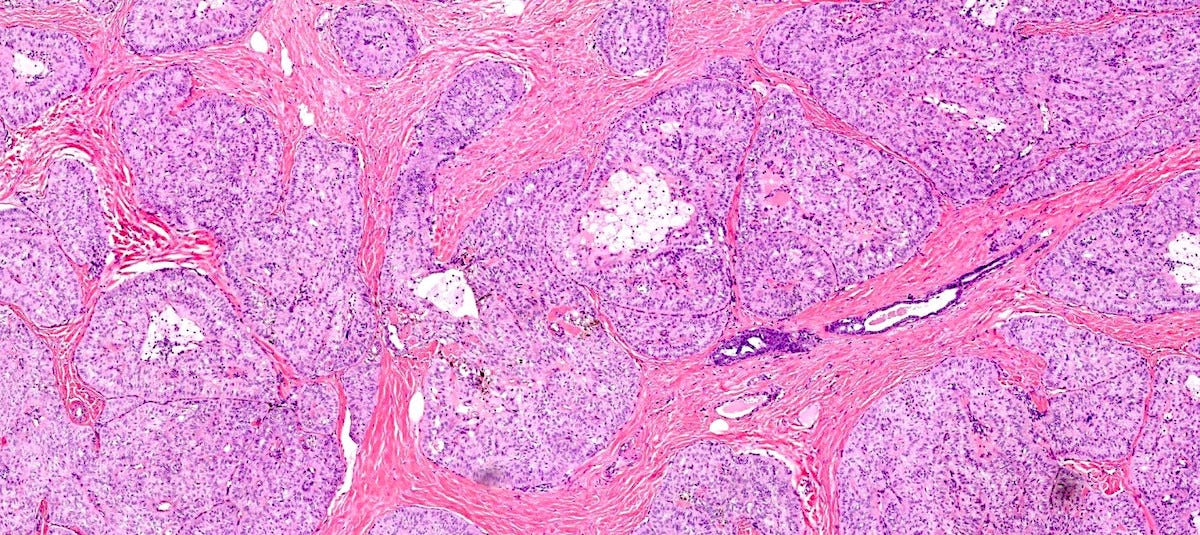

In reported cases, the tumor appears as a well circumscribed, firm mass. Microscopically, reported cases exhibited a wide spectrum of growth patterns, including solid nests, trabeculae, tubules, cribriform structures, strands and fascicles. In these cases, the tumor cells were monotonous with uniform nuclei and scant cytoplasm, lacking significant pleomorphism or mitotic activity.

Polymorphic carcinoma - microscopic images

Note: due to its rarity in the breast, these images are from the similar tumor in the salivary glands